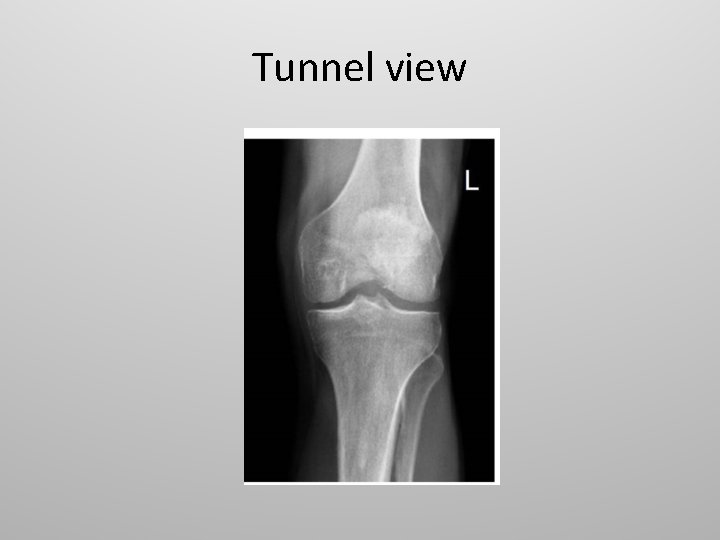

Tunnel view